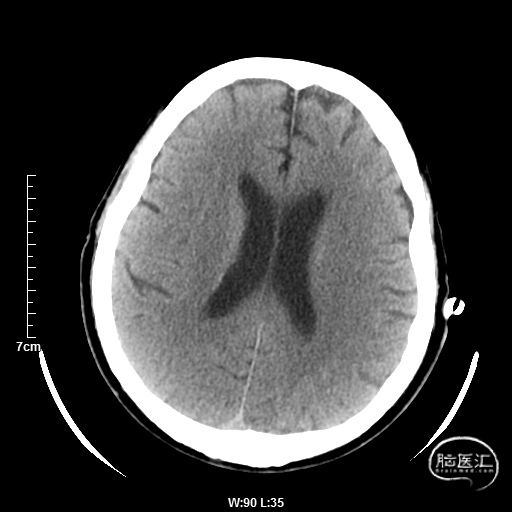

术后第一天:神志清楚,言语正常,头晕,共济失调,双侧瞳孔等大正圆,直径3mm,对光反射灵敏,四肢肌力5级,NIHSS评分1分。

术后第九天:恢复出院。

术后半年CTA:Bridge支架形态及贴壁良好,前向血流正常。